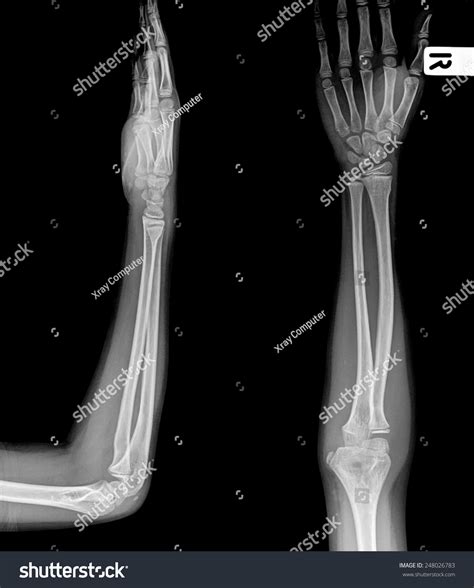

A forearm X-ray is one of the most common diagnostic imaging procedures performed in emergency departments, urgent care centers, and orthopedic clinics. Whether you have suffered a sudden fall, a sports-related injury, or are experiencing unexplained chronic pain, this imaging tool provides doctors with a vital, non-invasive look beneath the skin. By utilizing small amounts of electromagnetic radiation to create images of the bones in the forearm—specifically the radius and the ulna—medical professionals can accurately diagnose fractures, dislocations, and various other structural abnormalities. Understanding the procedure, why it is requested, and what the results mean can help demystify the process and prepare you for your visit to the radiology department.

To interpret a forearm X-ray, it helps to understand the anatomy involved. The forearm consists of two long bones that work together to allow for flexibility and rotation:

The Radius: Located on the side of the thumb, the radius is the bone that primarily allows the forearm to rotate, enabling you to turn your palm up or down.

The Ulna: Located on the side of the pinky finger, the ulna is larger at the elbow and helps form the hinge joint necessary for bending the arm.

Anteroposterior (AP) View The arm is flat on the table, palm facing up, providing a front-to-back view of the radius and ulna.

Lateral View The arm is turned 90 degrees, showing the side profile of the bones to check for displacement or angling.

Once the forearm X-ray images are captured, they are sent to a radiologist—a doctor who specializes in interpreting diagnostic images. They will look for: